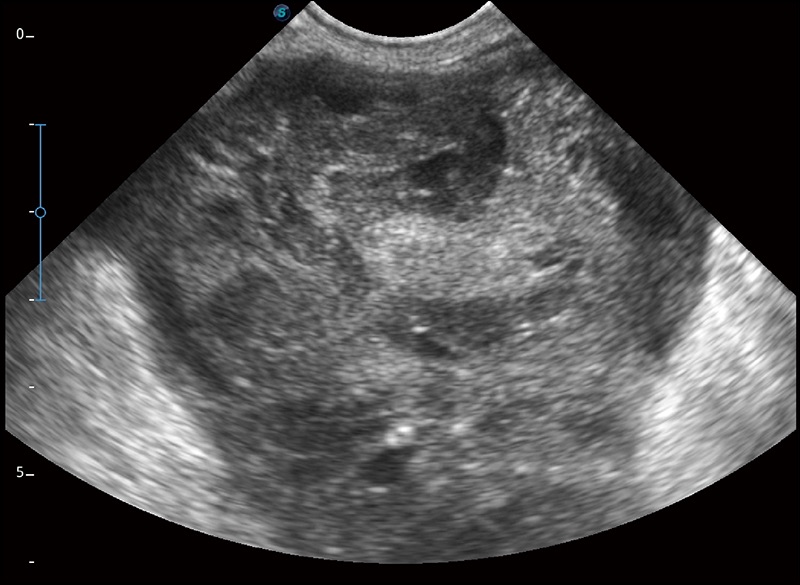

α1卓越的圖像質(zhì)量和便捷的工作流程,使每位寵物醫(yī)生都能輕松掃查。其全面的獸用應(yīng)用功能和緊湊型的結(jié)構(gòu)設(shè)計(jì),可以滿(mǎn)足動(dòng)物檢查的多種需要。專(zhuān)業(yè)的預(yù)設(shè)檢查模式和多領(lǐng)域測(cè)量軟件包有助于為不同類(lèi)型的動(dòng)物提供檢查, 讓寵物醫(yī)生能夠出色的完成工作。